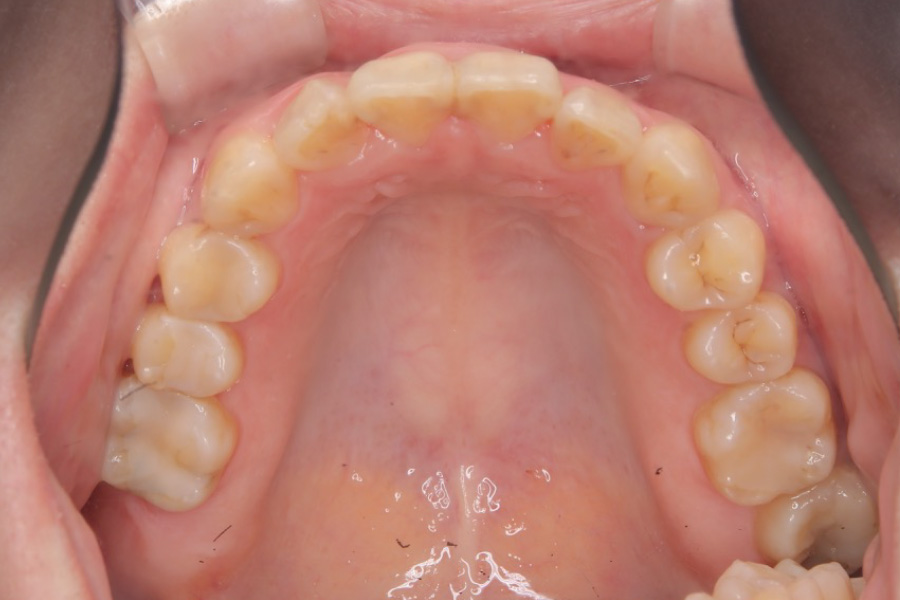

治療後

主訴 全体のガタつきが気になる

治療内容 インビザライン矯正

非抜歯

治療に伴うリスク 矯正終了後は、リテーナーを指示通りに使用し、歯の後戻りを防ぐ必要があります。